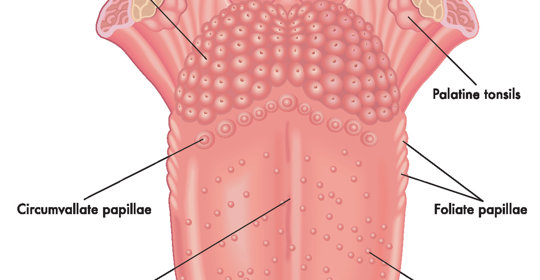

口唇麻木感刺痛:舌下神經調節與舌炎區別與處理